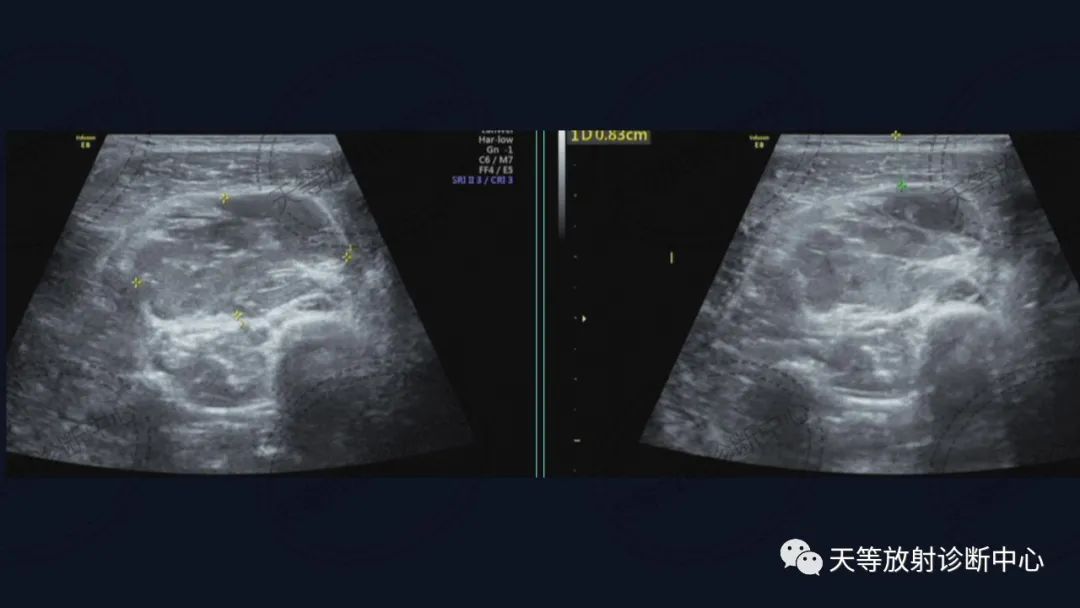

病例,儿童男性

血管瘤

组织学上主要表现为血管管道数目的增加及纤维结缔组织、平滑肌、炎性细胞和毛细血管、淋巴管等不同程度的浸润。MRI观察病灶内纤维结缔组织呈分隔状及线状低信号影,含血管成分可表现血管流空信号影。病灶内出血表现信号混杂等。